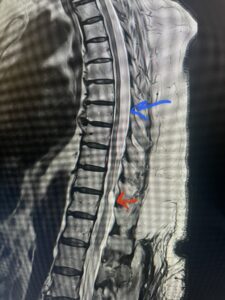

Fig. 1 Sagittal T2-weighted thoracic MRI demonstrating both T10-11 focal intradural arachnoid cyst (red arrow) and larger upper thoracic cyst that appears to extend from T4-T8 (blue arrow).

This 47-year-old male who four months prior was lifting weights developed sharp pain in his neck. After that he developed progressive numbness in his arms, neck pain and headache. He said that the right arm was worse than the left. On examination the patient had long tract weakness on the right side which included his triceps, finger extensors, hip flexors, and dorsiflexors. The patient did not have hyperreflexia. MRI (Fig. 2) demonstrated a massive, extruded disc herniation with severe cord compression. The patient because of progressive myelopathy and spinal cord compression was indicated for anterior cervical discectomy and fusion at C4-5 (Fig. 3). Patient had significant improvement of weakness and numbness post operatively.

Fig. 2a Sagittal T2-weighted cervical MRI demonstrating large C4-5 herniated disc with spinal cord compression (red arrow)